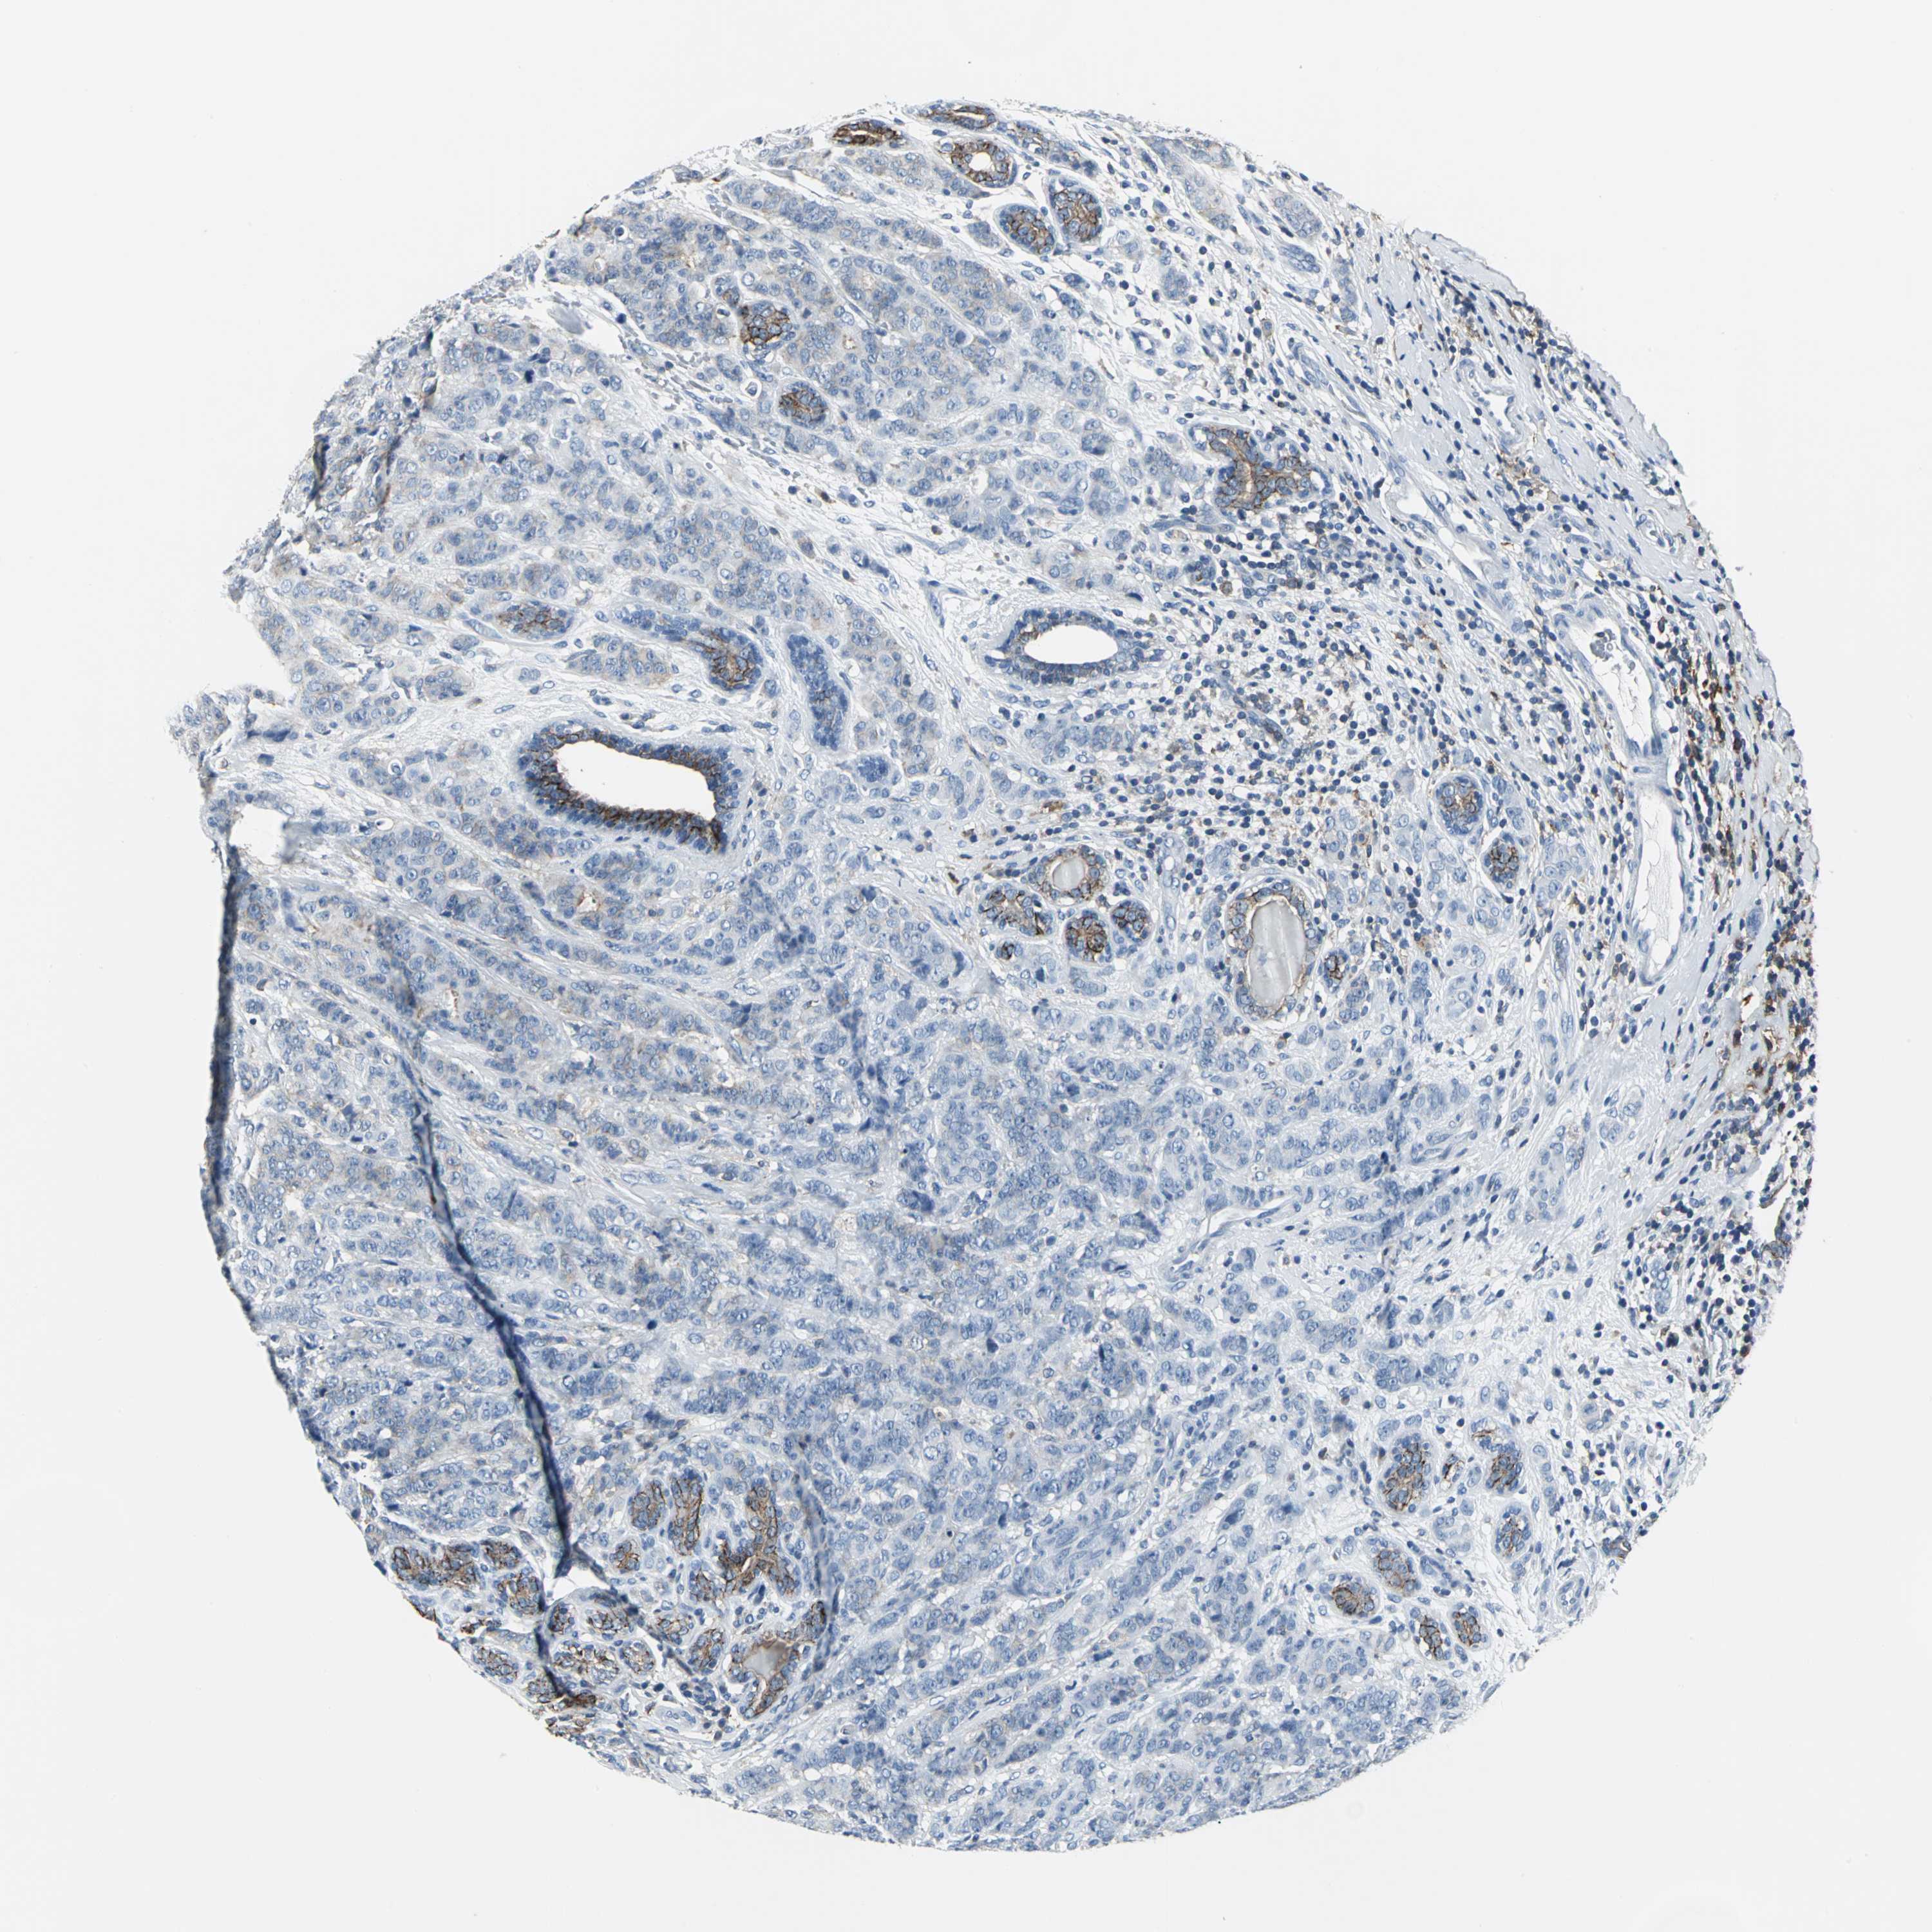

CANCER BREAST CANCER Show tissue menu

BRCA TCGA BRCA VALIDATION PROTEIN EXPRESSION